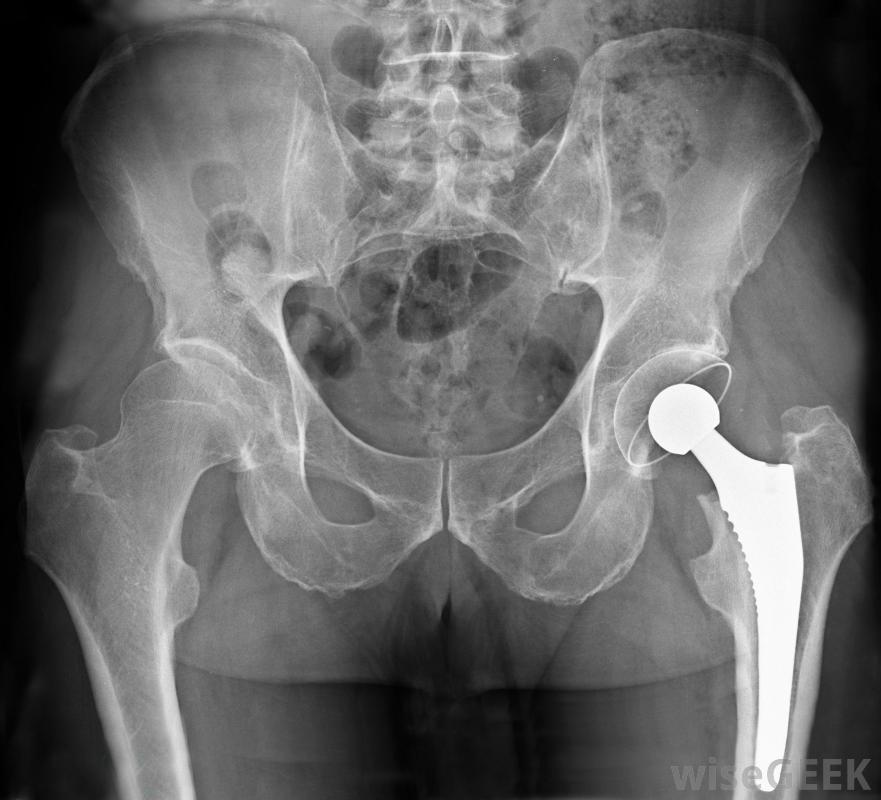

骨水泥是髖關節置換手術中使用的一種物質,它作為粘合劑將人工髖關節固定在適當的位置。它可以是預先混合的形式,也可以是手術過程中在手術室中混合的粉末和液體。骨水泥也可以用來填充骨頭上的任何洞或裂縫,并且可能含有抗生素來防止感染。一旦混合,粘合劑就會變成糊狀或糊狀物質,在幾分鐘內凝固。骨水泥用于髖關節置換手術,將腿部股骨頭固定在人工髖關節上骨水泥的性能由聚甲基丙烯酸甲酯(PMMA)組成。這種塑料也用于不易破碎的玻璃、浴缸,它是髖關節置換術中的一種標準粘合劑,用于將腿的股骨頭連接到人工髖關節上。用這種物質進行的髖關節置換手術通常可以使用幾十年骨骼解剖圖。外科醫生也在椎體成形術中使用骨水泥來治療骨質疏松癥醫生用x光片和一個觀察屏幕來確定將密封劑注入脊柱的針頭的位置。在這個過程中,粘合可以減輕骨質疏松引起的壓縮性骨折引起的疼痛2010年,研究人員資助了人體試驗,探索骨水泥用于修復退伍軍人頭部和面部的損傷。一種能促進骨生長的物質可以注入骨水泥中,從而消除了用金屬板修復骨折的必要性。這種粘合劑的使用也可能對骨折的胳膊和腿起作用在事故中骨折。當抗生素加入骨臼時,它有助于減少感染。細菌感染會阻礙骨骼的再生,如果暴露在空氣中的開放性骨折被某些細菌侵入,可能會導致截肢。動物研究表明,在加入特定抗生素后,將這種產品注射到骨折處可以防止葡萄球菌感染心臟外科醫生在心臟直視手術后使用非合成骨水泥來封閉胸骨。聚合物骨水泥由蓖麻籽中的甘油三酯和氯化鈣組成,心臟手術后的疼痛大多來自于打開胸骨進入心臟,心臟通常用金屬絲封閉。使用骨水泥后,胸骨通常在24小時后完全穩定心臟外科醫生在心臟直視手術后使用非合成骨水泥封閉胸骨。